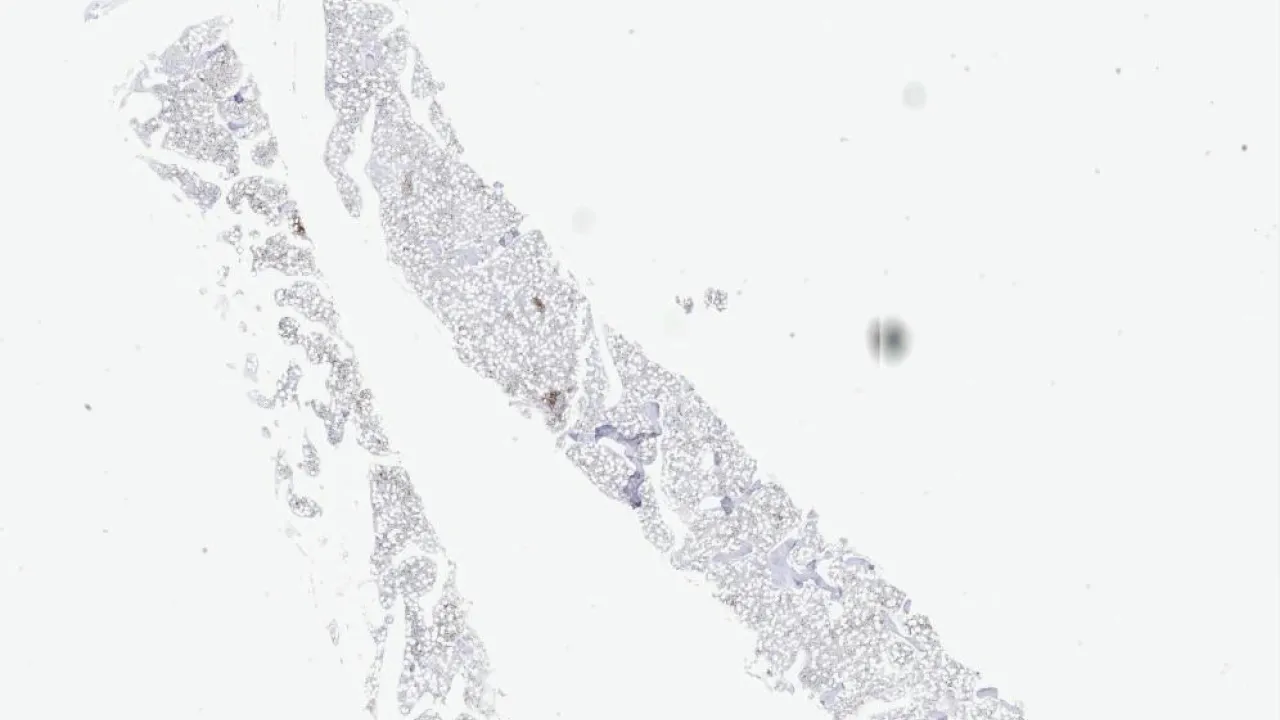

Bone Marrow, systemic mastocytosis, CD3 stain